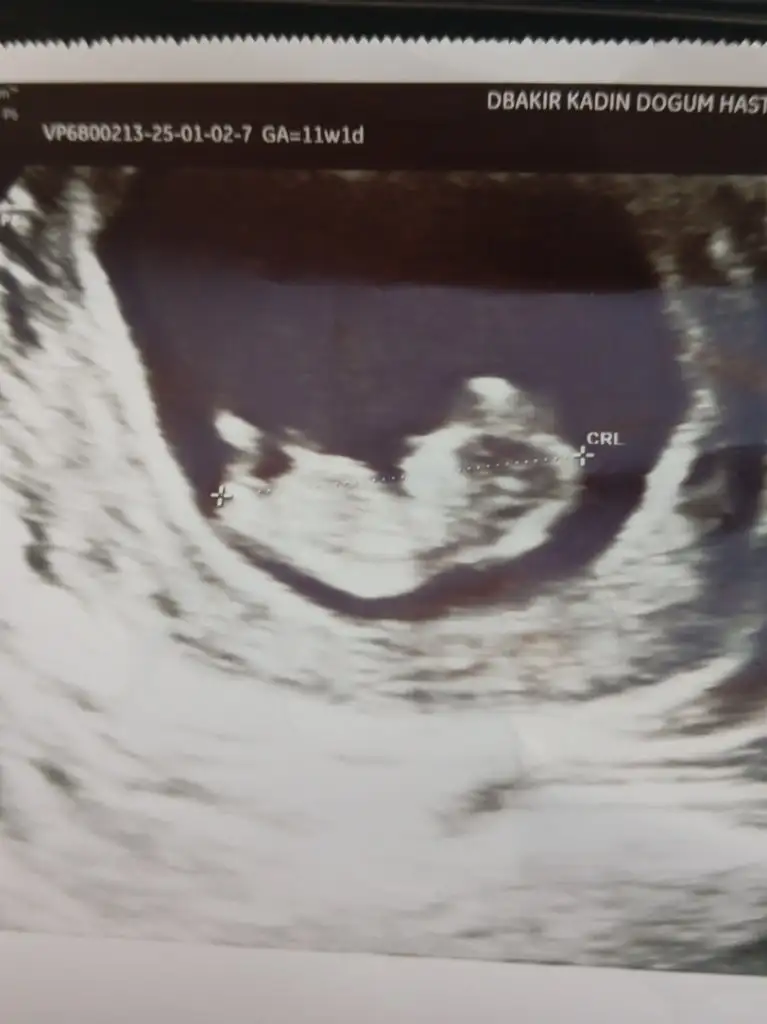

Nub veya Ramzi Theorisi anlayan var mı?

Burda ise eğer gördüğüm nub ise kız bebek tahminim. Gönlünüzce olur umarım 🙏